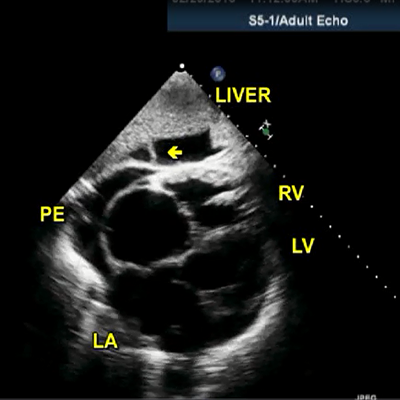

Large PE

|

950 KB

Large PE. Mild TR

|

915 KB

Large pericardial thrombus

|

997 KB